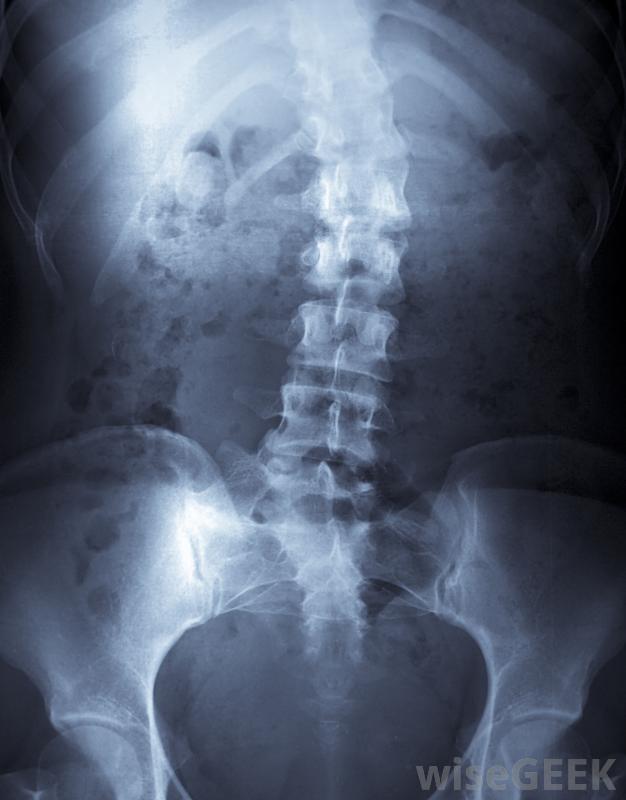

治疗和管理。最常见的矫形器械之一是矫形插入物,它在鞋子中提供足弓支撑。矫形设备也常用于外伤事件(如车祸)后,以支撑可能受伤的脊椎。患有影响肌肉骨骼系统疾病的儿童可能需要佩戴矫形器械以确保肌肉和骨骼的健康和功能性生长和发育。

矫治器可用于短期和长期治疗。在肌肉损伤愈合时,为了防止可能再次损伤肌肉的运动而使用的支架就是短期矫形器械使用的一个例子长期使用在遗传病治疗或严重创伤的情况下更为常见,如果不使用该器械,将导致严重的行动受限或残疾。肌营养不良和脊柱侧凸是两种需要长期使用矫形器械的遗传疾病。老年人可能需要矫形器械行动能力,特别是当他们患上严重的关节炎或其他限制活动或使运动疼痛的情况下。

脊柱疾病性脊柱侧凸通常需要长期使用矫形外科手术矫正器具。